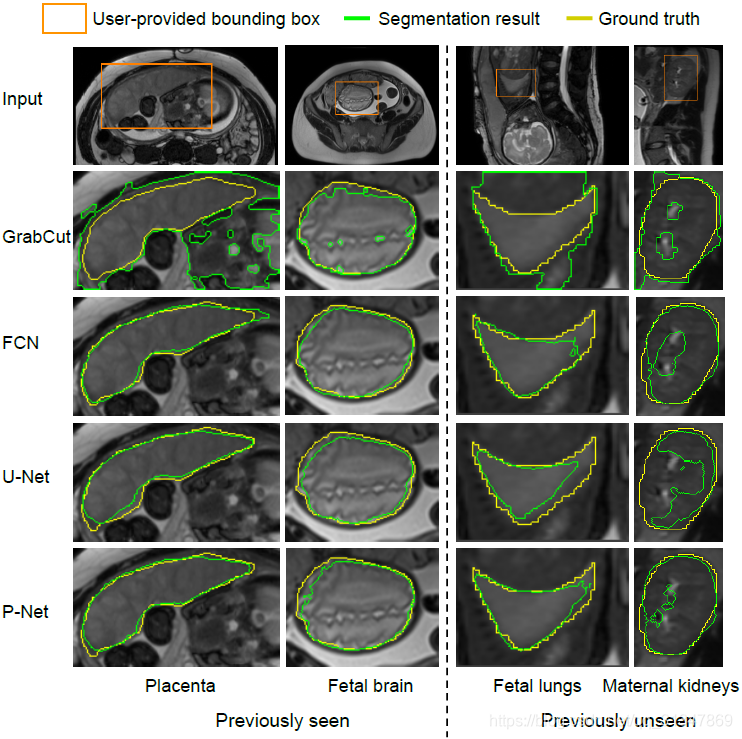

(1)对比 GrabCut,FCN,U-Net 和本文提出的 P-Net 的初始分割结果:

GrabCut 只有在对比度比较大的脑部图像上分割效果比较好

对于训练过的特定目标:Placenta 和 Fetal brain,FCN、U-Net 和 P-Net 取得的分割效果差不多,都很接近 ground truth

但是对于未见目标:Fetal lungs 和 Maternal kidneys,P-Net 的分割结果明显比 FCN 和 U-Net 好很多

具体比较如下:从表中可以看出 P-Net 虽然在 Placenta 和 Fetal brain 上的分割效果不比 FCN,但是对于未见目标的分割效果是最好的。